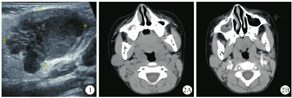

男,6岁,3个月前无意中发现右侧耳下区有一肿物,约大拇指大小,局部无肿胀疼痛、无皮肤瘙痒及破溃糜烂等不适,后肿块缓慢增大,约核桃样大小,于2019年2月来院就诊。体检:右侧耳下区可及肿块,大小约2 cm×2 cm,质中,界清,活动可,表面皮肤完整,口内腮腺导管口无红肿,分泌物清亮,无口角歪斜、鼓气漏气、鼻唇沟变浅等,右颈部未及异常肿大淋巴结。B型超声检查示右侧腮腺内见2.8 cm×1.9 cm×1.7 cm混合性回声肿块,边界尚清,形态不规则(图1)。CT检查示右侧腮腺内见一团块状软组织密度影,大小约2.0 cm×2.0 cm,形态欠规则,密度略欠均匀,增强后呈轻中度不均匀强化,颈部散在淋巴结显示(图2)。实验室检查未见明显异常。随后在超声引导下穿刺,穿刺病理示淋巴上皮癌。排除手术禁忌证后,患儿于2019年3月15日在全身麻醉下行"右侧腮腺恶性肿瘤局部扩大切除术"。手术可见肿瘤位于腮腺浅叶后份,约1.5 cm×1.5 cm大小,与面神经颊支及下颌缘支粘连明显,将肿瘤及邻近腺叶组织一并切除,并进一步扩大切除粘连部分咬肌,术后标本送检。病理检查肉眼观:灰白结节一枚,大小2.7 cm×2.0 cm×1.8 cm,切面呈实性,灰白质中,带包膜;镜检可见肿瘤细胞不规则岛状排列,细胞呈合体细胞样,胞质淡嗜酸性,胞界不清,卵圆形泡状核,核仁明显,间质见较多以小淋巴细胞为主的炎细胞,反应性淋巴滤泡形成(图3)。免疫组织化学检查示CK(+)(图4),P63(+),P40(+),P53(+),CD3(T细胞+),CD20(B细胞+),CD8(T细胞+);原位杂交检测可见EBER/对照(+)(图5)。病理诊断:(右侧腮腺)淋巴上皮癌。术后患儿恢复可,切口愈合佳,无耳垂周皮肤麻木不适等耳大神经损伤症状,无流涎流液、鼻唇沟变浅、鼓颊鼓气乏力等面神经受损症状,予出院,嘱休息2~3周后放疗科门诊复诊,行局部辅助放疗。患儿术后1个月至我院放疗科就诊,复查腮腺MR提示右侧腮腺下部斑片状异常信号(图6A、图6B),术后改变?两侧颈部及颌下多发淋巴结肿大(图6C)。临床考虑不能除外腮腺LEC局部淋巴结转移的可能。结合患儿年龄较小,颈部淋巴结清扫术难免造成相应功能障碍,影响生活质量,故欲行单纯性肿块及周边、腮腺淋巴结引流区照射放疗,患儿家属要求出院,至上级医院进一步诊治。本例随访15个月,术后赴上级医院行PF方案(顺铂+氟尿嘧啶)化疗一周期,右腮腺区放疗95%PTVtb 60Gy 30次,过程顺利,颈部肿大淋巴结消退,未见局部复发及远处转移。

腮腺LEC早期大多数表现为单侧生长缓慢的无痛性肿块,晚期可侵犯周边组织并固定,活动度差,侵犯面神经可伴随面神经麻痹症状的出现,如面部表情肌瘫痪、鼻唇沟变浅、口角下垂、鼓腮乏力等[9]。相关文献报道10%至50%的LEC患儿在发病时出现颈部淋巴结受累[14]。在本病的诊断中,超声检查最为简单易行,初诊时也常常采用,肿块常表现为形态不规则,边缘不清晰,内部回声以低回声为主,较为杂乱[15]。由于超声检查的局限性,临床工作中为了进一步鉴别诊断,多需完善增强CT或MR检查。在CT扫描中,大多数LEC呈单发、实性占位、界限不清、分叶状、均匀等密度或稍低密度,少见囊性变、钙化、中度或明显均匀强化[11]。在MR检查中,病灶T1WI呈等信号,T2WI呈稍高信号;增强后均匀或不均匀中度及以上强化。肿大淋巴结强化与腮腺病灶一致,较大者呈环形强化[16]。但该病的临床表现及影像学检查常常是非特异性的,难以明确诊断,故其确诊还需借助组织病理学检查。其病理形态学特征与鼻咽部非角化性癌没有明显区别[1]。即肿瘤细胞呈大的合体细胞样,胞质淡嗜酸性,胞界不清,核呈圆形或卵圆形泡状,核仁清晰,间质内有丰富的淋巴浆细胞浸润,常可见反应性淋巴滤泡。免疫组织化学检测显示肿瘤细胞的细胞角蛋白(cytokeratin,CK)阳性,间质包含CD20阳性的B淋巴细胞和CD3、CD8阳性的T淋巴细胞。尤其重要的是,LEC与EB病毒感染的关系,原位杂交中肿瘤细胞核对EBV编码RNA(EBV encoded RNA,EBER)呈阳性[1]。故腮腺LEC诊断前需排除鼻咽癌的转移。本例行鼻咽部检查及头颈部CT均未发现鼻咽部新生物,结合病理检查结果,考虑为原发性腮腺淋巴上皮癌。